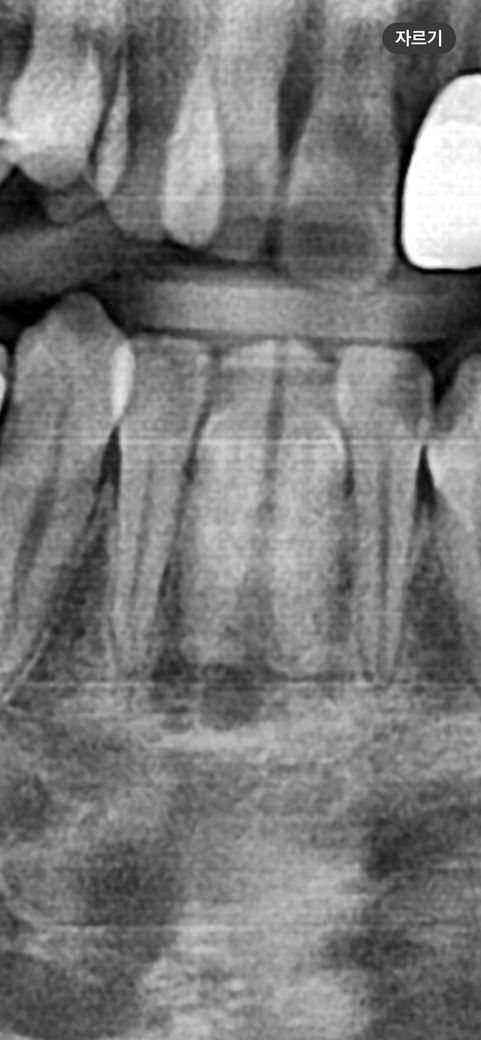

앞니 뿌리 염증인가요 약간의 증상있으나 심한정도는 아닙니다

이거 치아뿌리 염증인가요? ㅠㅠ

*사진은 9개월전 교정하기 전 입니다.

현재 치아 교정중인 사람인데요 앞니가 평소에는 괜찮다가 스프링붙이고 공간벌리기 끝나고 스프링 떼고 난 후에 압력? 약간의 시큰거림(특히 양치 후)이 있습니다 그리고 해당앞니는 예전부터 초기충치가 있던 치아이구요 초기충치 발견당시(9개월전)에 신경을 계속 쓰니까 증상이 있다가 신경안쓰니까 사라졌다가 최근에 증상이 조금 있어요 교정때문인지 충치 때문인지.. 또 치과를 몇군데 갔었는데 초기충치를 다들 잘 발견 못 했고 짚어줘야 알았습니다 문제 있는 치아인가요? 신경치료,발치 등 해야하나요?

사진으로 보이는 충치만으로는 치근단 질환이 생길 정도는 아닌 것으로 보입니다. 방사선상 어두운 부분이 보이긴 하나 치근단 질환을 확인하기 위해서는 CT 촬영 등에 정밀한 검사가 필요할 수 있습니다.

엑스레이 사진 순서에 있어서 젤 왼쪽이 가장 최근이라면 염증이 잡히고 있는 상태라고 볼 수 있겠으나 파노라마 사진 말고 치근단 사진이 좀 더 정확합니다